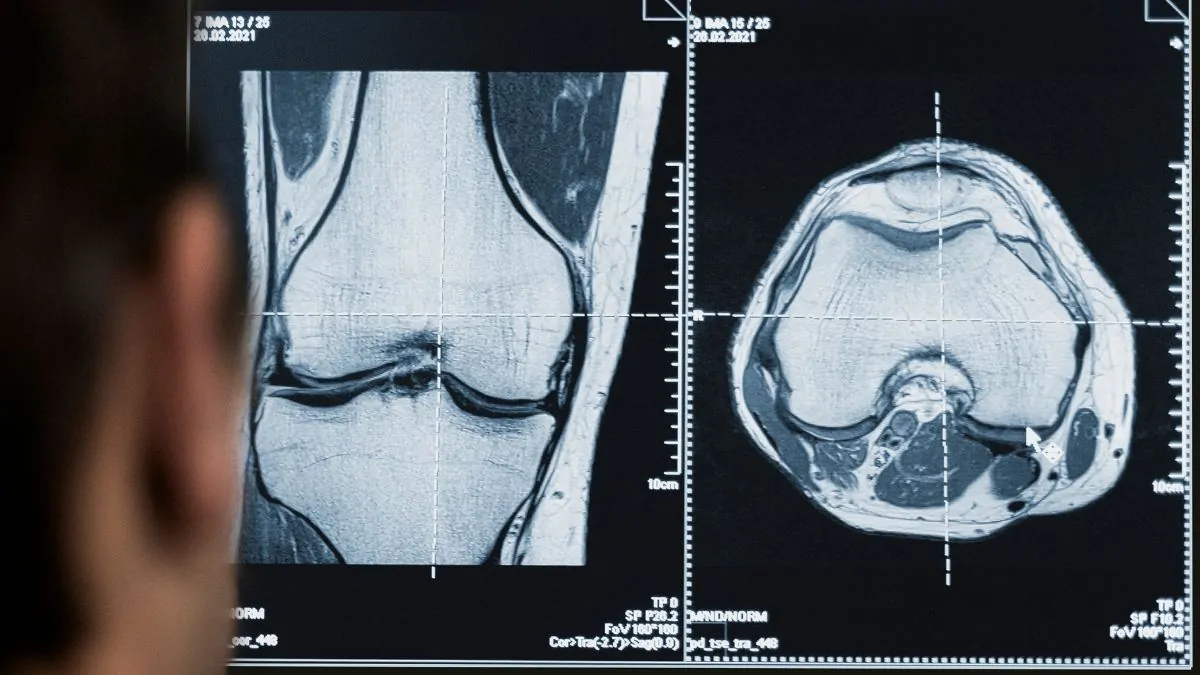

El campo médico evoluciona entre cambios y avances constantes con el fin de mejorar la calidad de atención y tratamiento de los pacientes. Siendo así, la incorporación de la tecnología resulta siendo una pieza clave en muchos procedimientos médicos. En términos de imágenes diagnósticas, cuando esta se usa en radiología, se facilitan y mejoran diferentes intervenciones requeridas para casos de fracturas de huesos, detección de tumores, lesiones, neumonías, y más. De allí que los avances tecnológicos en radiología se destacan en dos aspectos: el ambiental y el tecnológico, que son necesarios para optimizar el cuidado y la atención. Ambos enfoques cuentan con distintos puntos de interés que pueden ser evaluados y potenciados.